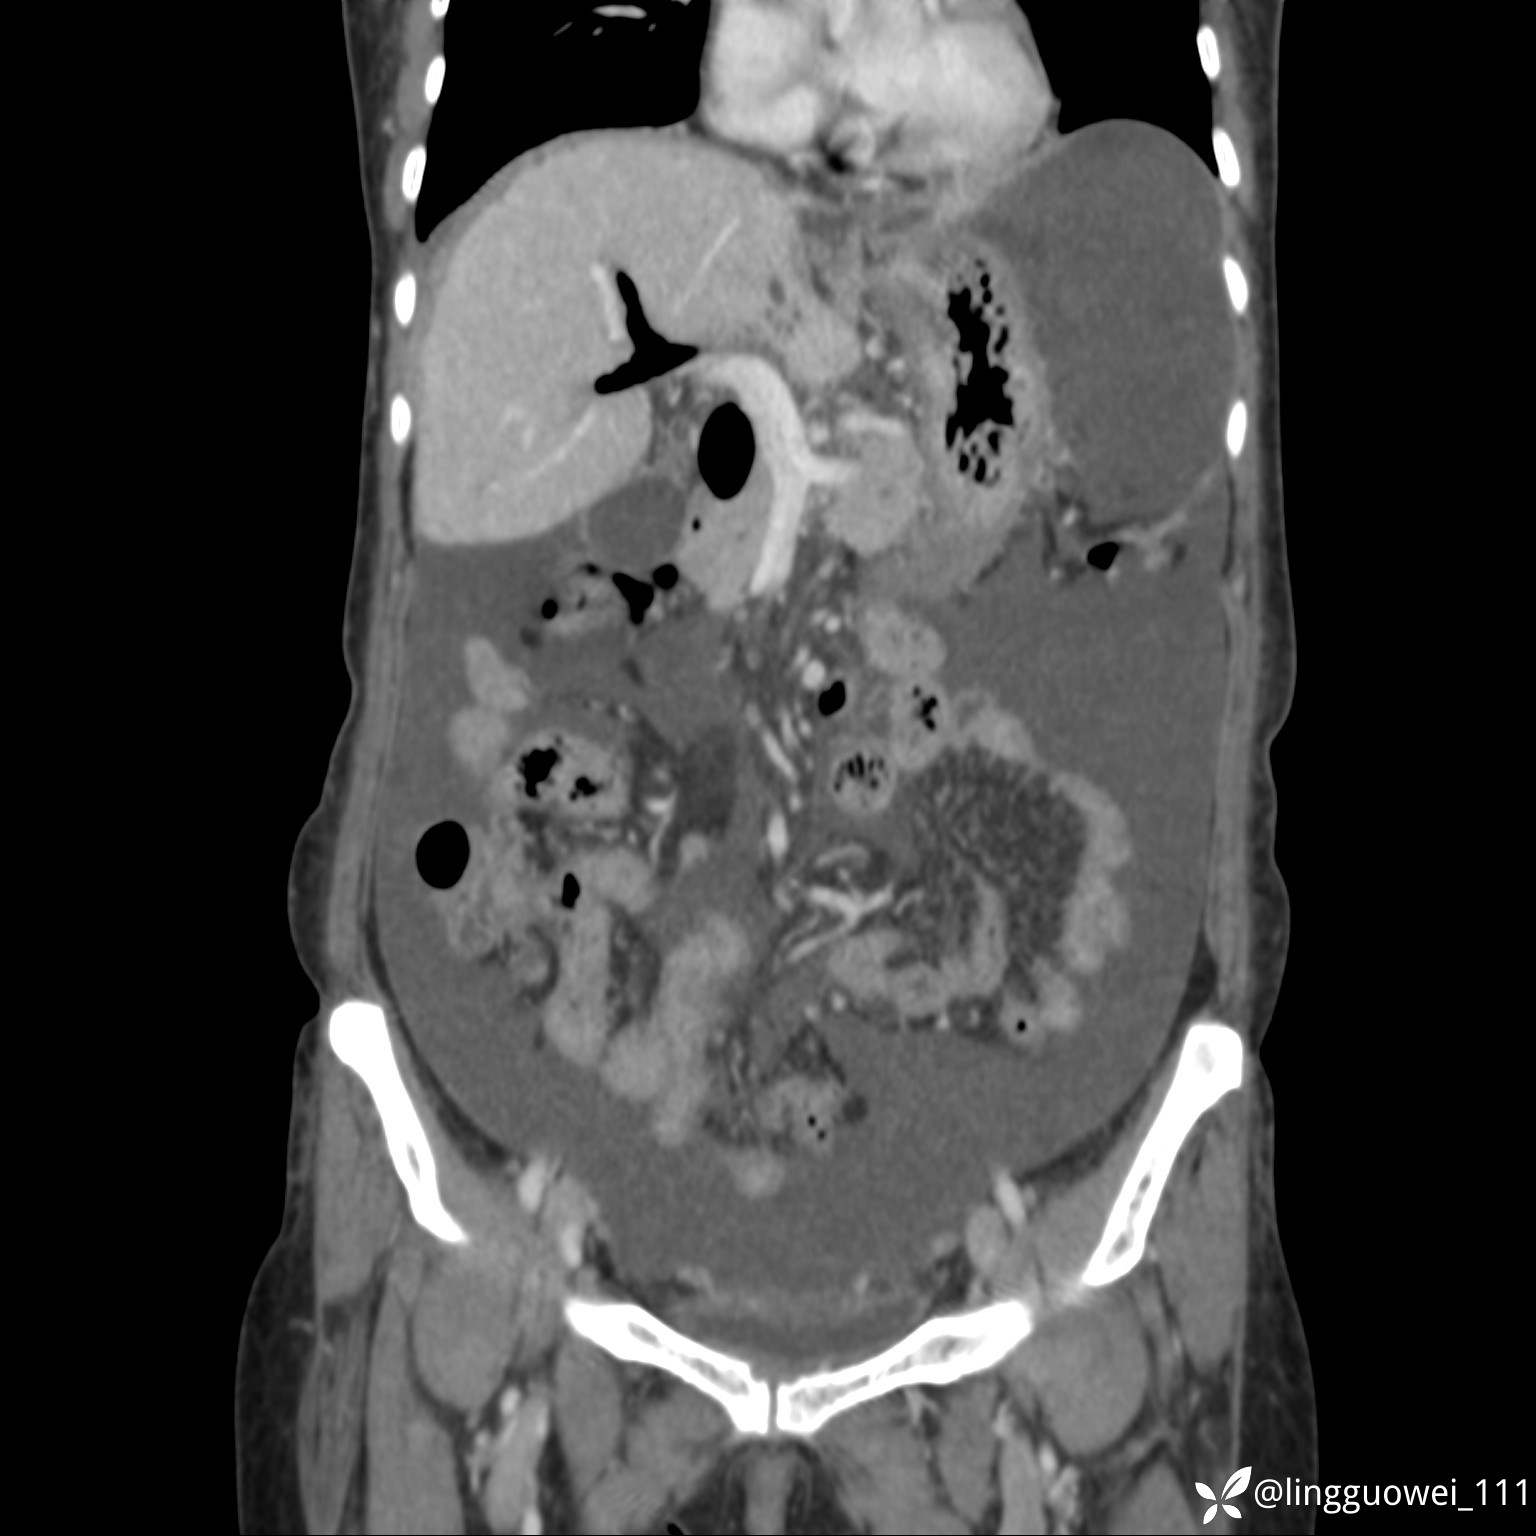

病例女,65岁,门诊行胃肠镜检查后,说腹胀入院检查,CT能发现病因吗?已公布结果

主诉:门诊行胃肠镜检查后,诉腹胀,入院检查,肝有病变吗?腹膜及腹腔的表现有特征性吗?

门脉期:

img